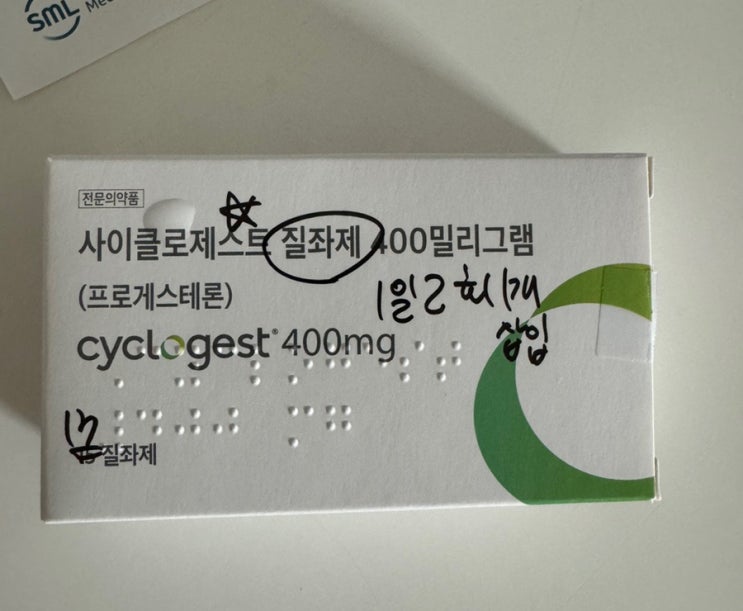

난포를 키우기 위해 페마라를 5일간 복용하고 배란초음파를 확인하러 병원을 방문했다. 다행히 난포도 잘 ...